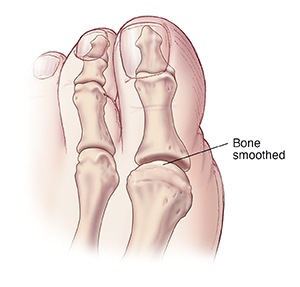

Cheilectomy

This is done when the arthritic joint and cartilage can be saved. A bone spur caused by arthritis may be on the top of the big toe joint. The procedure involves removing this bone spur, often with a small part of the top of the joint itself. You will need to wear a surgical shoe for a few weeks. Once the foot heals, joint movement can be restored.